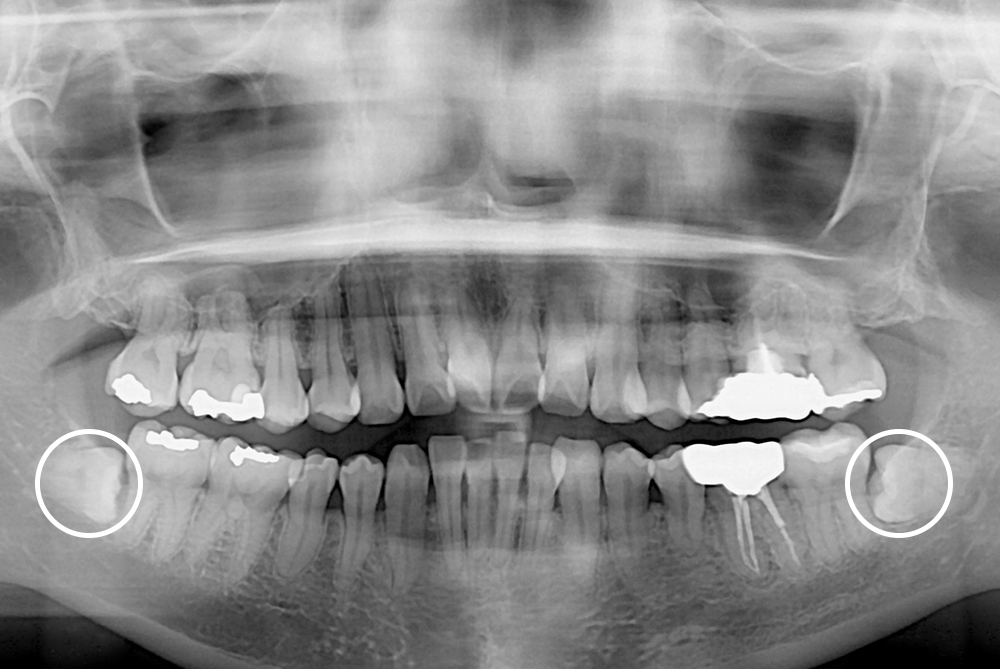

[사랑니] 매복 사랑니 발치

치료전 : 2017-08-15

세종치과는 구강악안면외과학 박사이신 원장님이 발치하는 치과입니다.